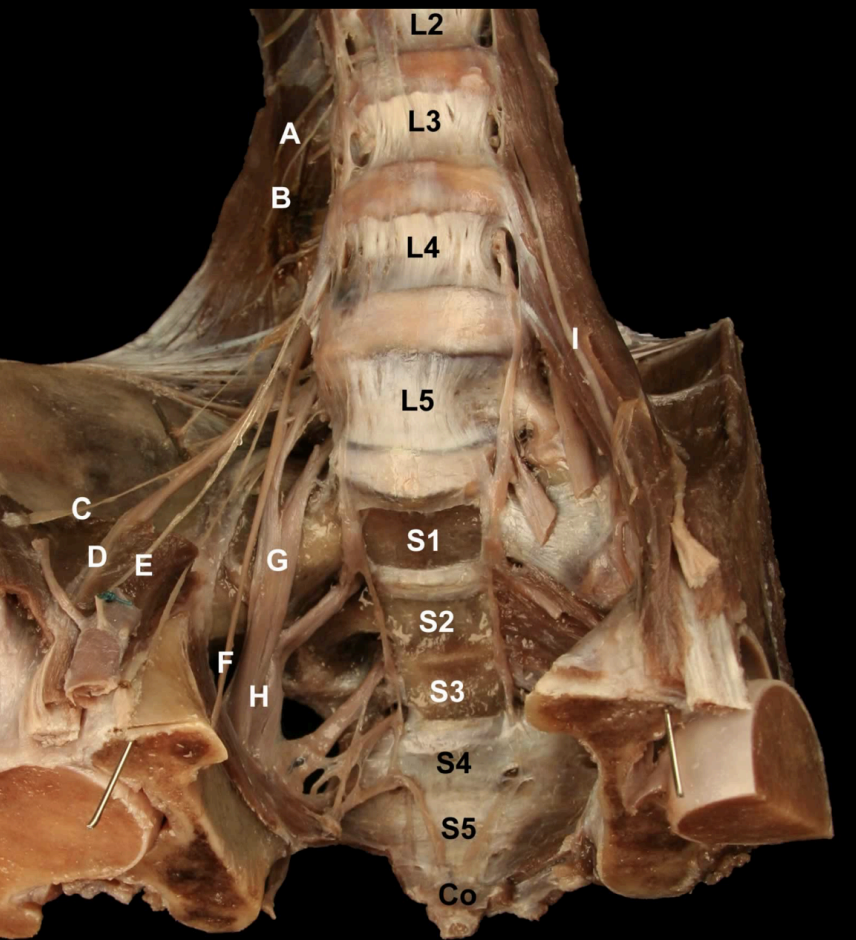

<p>Identify the Nerves and their corresponding nerve levels indicated on this <strong>Anterior view</strong> of the Pelvis:<strong> Lumbar Plexus</strong></p>

Identify the Nerves and their corresponding nerve levels indicated on this Anterior view of the Pelvis: Lumbar Plexus

A. Subcostal n (T12)

B: Iliophypogastric n (L1)

C: Ilioinguinal n, (L2)

D: Lateral Cutaneous n. of the Thigh (L2-L3)

E: Femoral n (L2-L4)

F: Genitofemoral n. (L1-L2)

G: Obturator n. (L2-L4)

H: Lumbosacral Trunk (L4-L5)